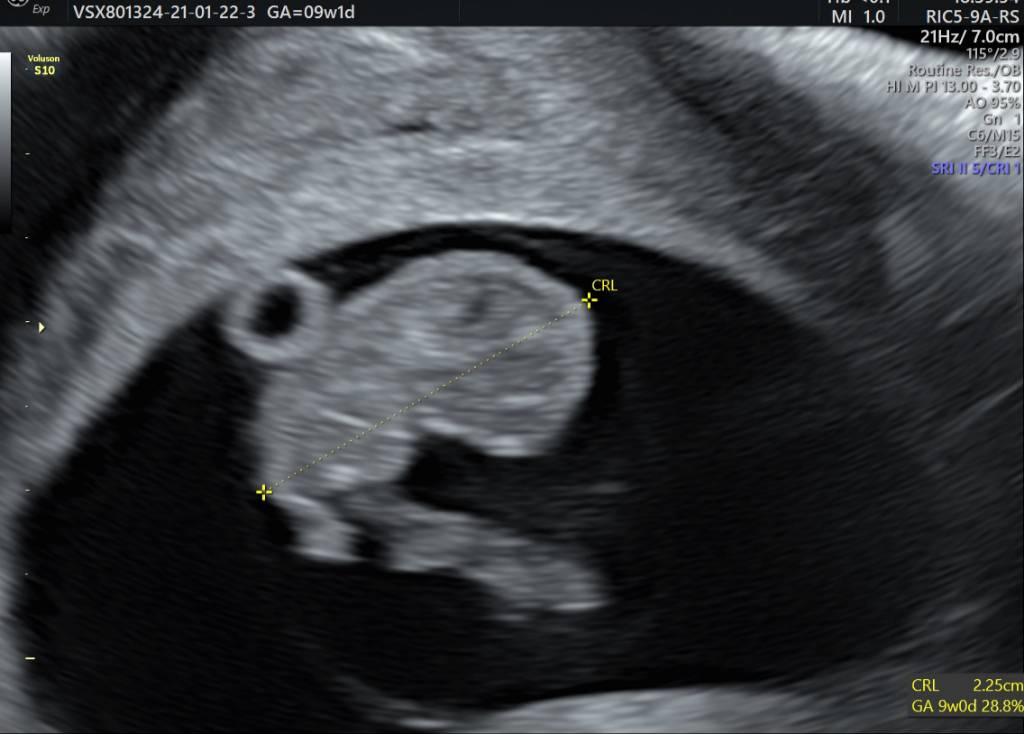

Dziewczyny pisałam już na prywatnym, ale części jeszcze nie ma w konwersacji także melduję się też tu po prenatalnych. Wszystko super, lekarka nie miała do niczego zastrzeżeń. Miałam usg przez brzuch i idealnie wszystko było widać. CRL 5.95cm, FHR 168/min, NT 1,6mm. Lekarz pooglądał wszystko dokładnie, czy są narządy, rączki nóżki i paluszki, kość nosowa też w porządku. Po usg zrobiłam test pappa. Na wyniki mam czekać około tygodnia. Ogólnie super długie usg, ponad 20 min mogłam oglądać dzidziusia. Pytałam o płeć i z dużą dozą pewności to dziewczynka, więc pokrywa się z moimi przypuszczeniami. Wg OM 12t0d, wg USG 12t3d, także idzie do przodu dziewczyna

Dziewczyny ja już po wizycie, mamy 2,25cm, pięknie bijące serduszko, które słuchałam [emoji3059] jutro będę się umawiać na prenatalne na 13.12 [emoji3526]